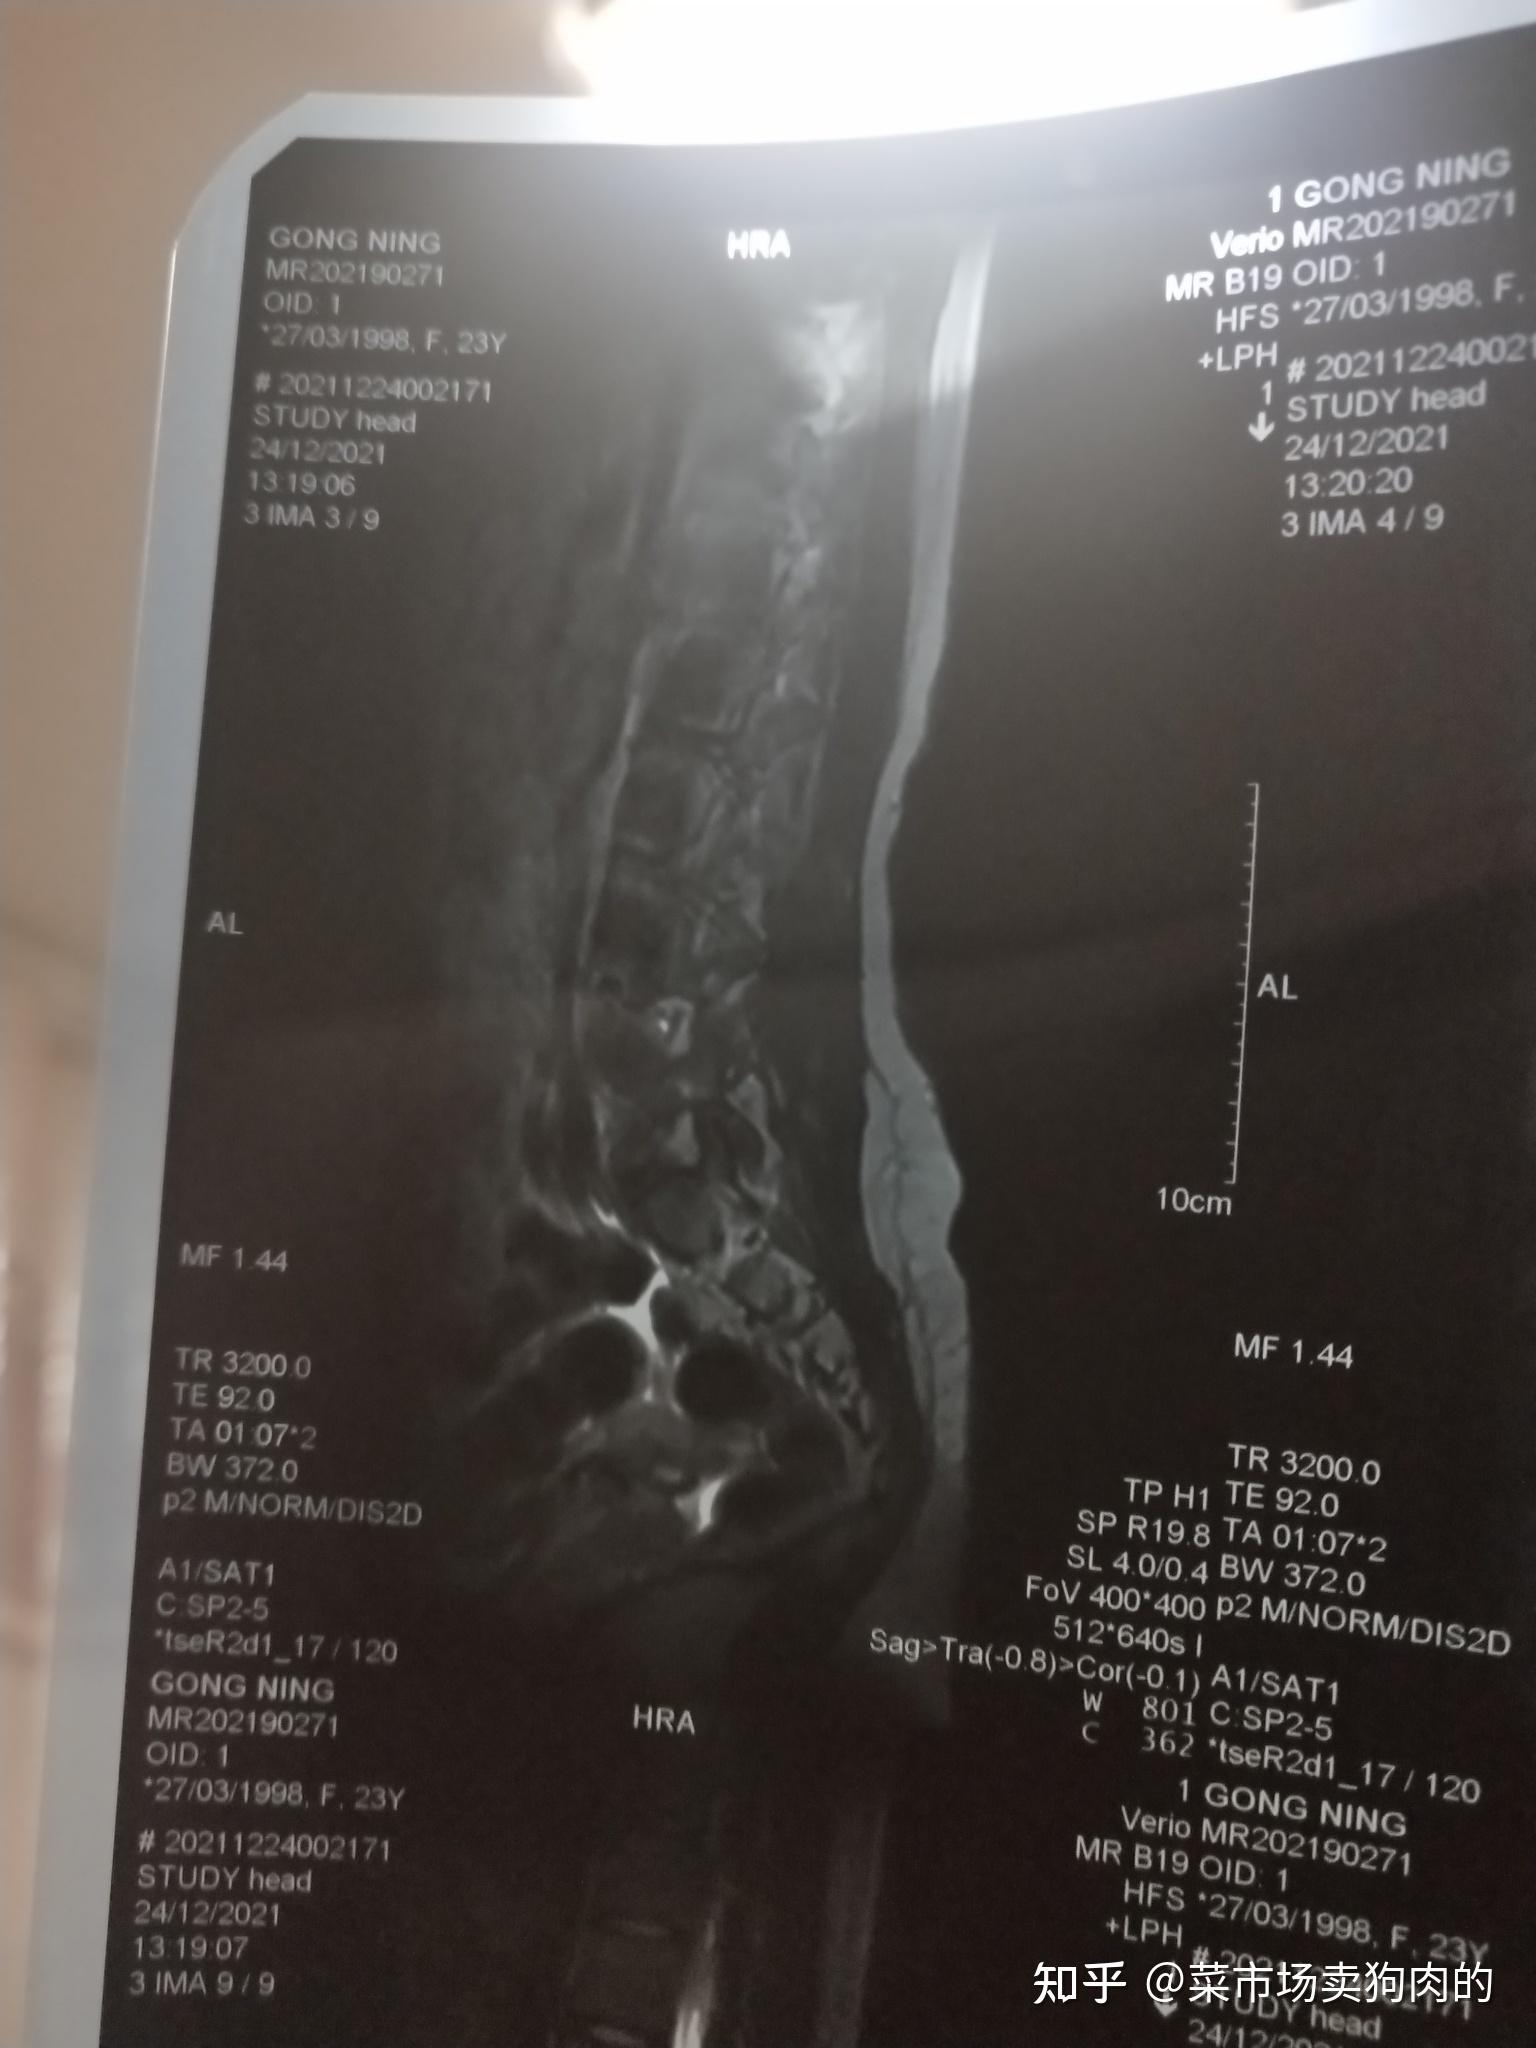

3、北京307医院以其先进的医疗设备资源闻名医院内的设备配置堪称一流,包括了多种高端技术仪器,旨在为患者提供全面且精准的医疗服务其中,PETCT核磁共振和螺旋CT用于精细的影像诊断,帮助医生详细了解病患的内部状况ECT发射型计算机断层扫描和数字减影机则在疾病检测中发挥着重要作用医院还配备了。